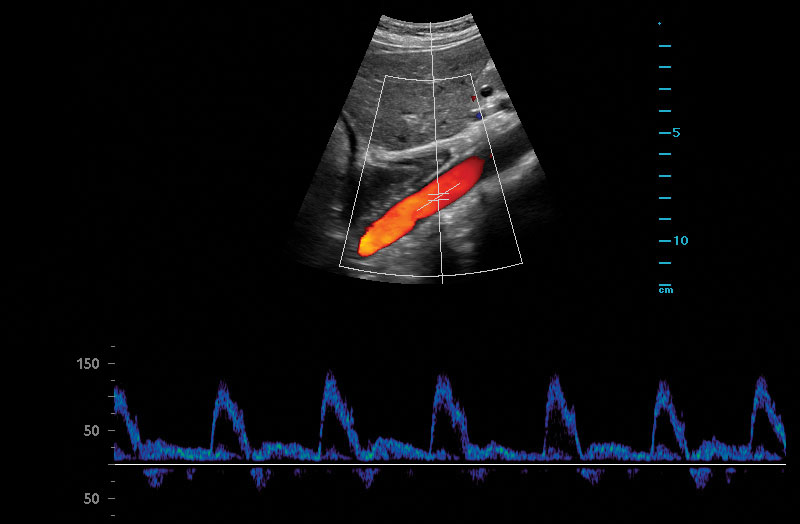

The Z.One PRO Ultrasound System Emerald Edition 2.0 is a powerful and portable advanced point-of-care imaging platform. Powered by software-based ZONE Sonography® Technology+ (ZST+), the Z.One PRO System provides optimal B-mode and Doppler imaging for patients, regardless of body habitus, helping ensure a reliable diagnosis. With a full family of transducers (from 2 – 20 MHz) and a wide range of applications, the Z.One PRO System is the imaging answer to your difficult clinical cases.

Advanced needle visualization technology allows increased needle visibility even during steep-angled procedures, while maintaining superior image quality. Improved confirmation of needle location in tissue minimizes harm to surrounding tissue.